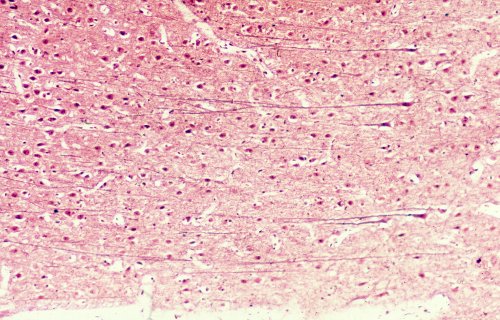

A very low magnification of the cerebrum demonstrating the different layers.

The cortex consists of 6 weakly differentiated layers.

A low magnification of the cortex from the area where the cells of Retz occur.

A high magnification of the cortex showing the cells of Retz (large pyramidal cells).